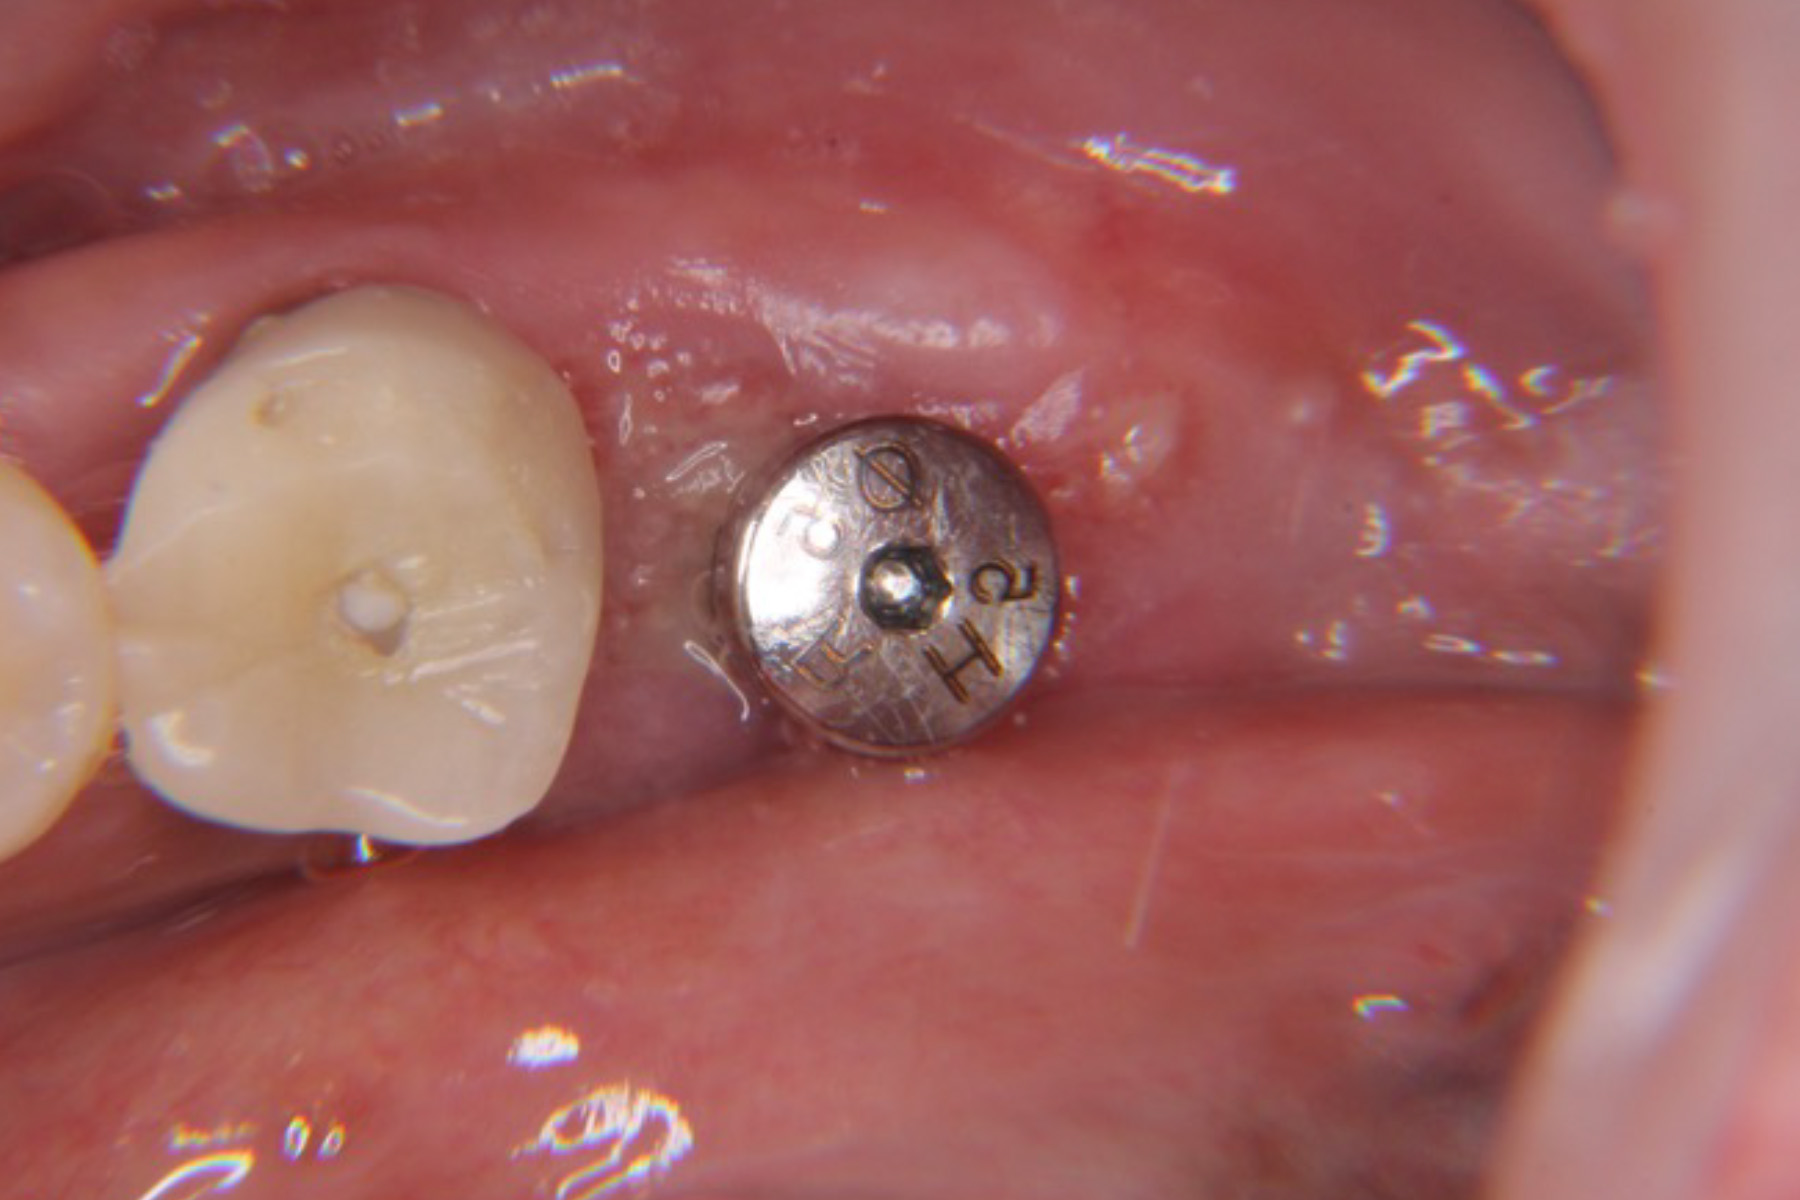

| 主訴 | 入れ歯が合わず使えない。インプラントを考えている。 |

| 治療内容 | 周囲組織に特別な処置は不要であった為インプラント埋入手術を実施した。 |

| 治療期間 | 3ヶ月 |

| 治療費 | 約¥500,000 |

| 治療リスク | 術後疼痛、腫脹。周囲組織の状態によっては追加の処置を要することもある。 |